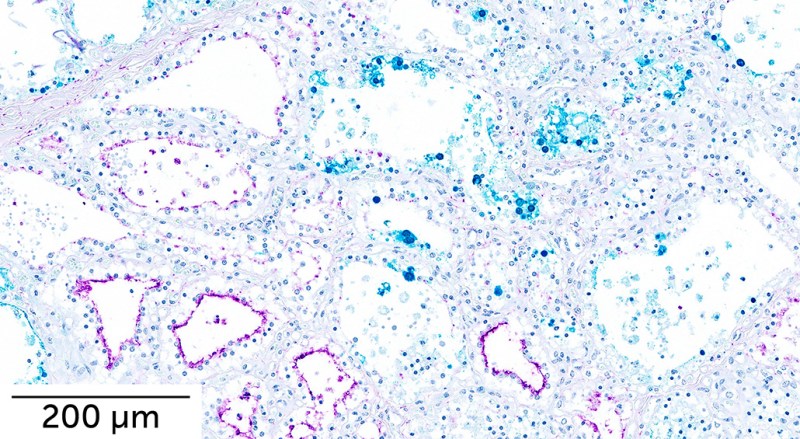

In mice and ferrets, the virus spread to the lungs, as well as throughout the body to organs including the brain, intestines, kidney and heart. The virus also spread to the mammary glands of mice and some ferrets.

Infected female mice could transmit the virus to pups feeding on milk, but no transmission occurred through direct contact, the team found. Just one of four ferrets exposed to infected animals in a neighboring cage showed signs of infection, suggesting that the virus circulating among cows still isn’t very good at spreading through the air.